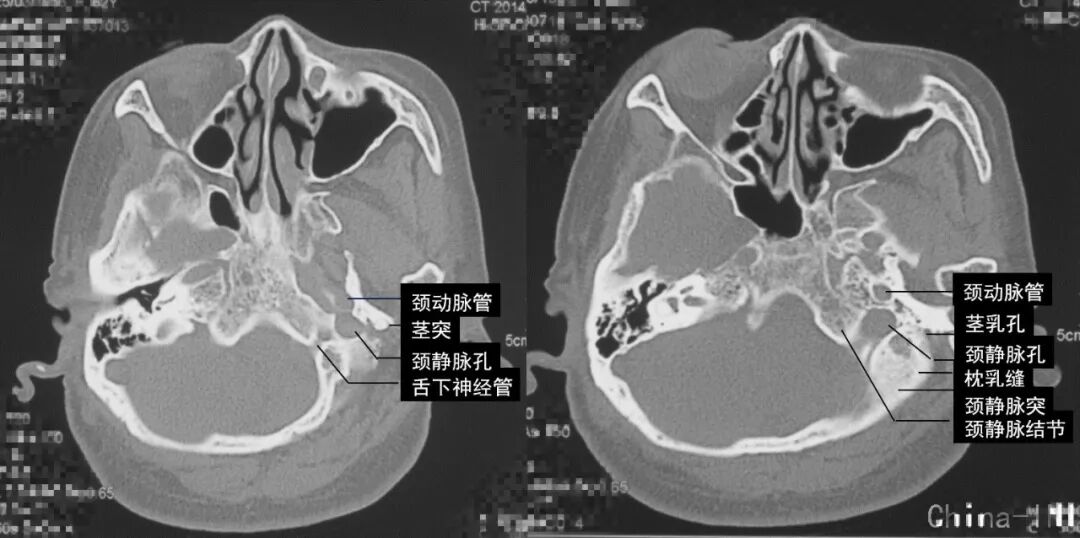

左侧颈静脉孔轻微扩大,边缘光滑,舌下神经管及颈动脉管未受累,这是神经鞘瘤的特征;如果是颈静脉球瘤,骨质会呈“虫蚀样”改变,破坏明显;脑膜瘤可伴有骨质增生。肿瘤外侧界为茎乳孔,为暴露颈静脉孔内肿瘤,术中需磨除枕骨颈静脉突。

颈静脉孔区位置深在,结构繁多,名称繁杂,方寸之间,颈内动脉、椎动脉、颈内静脉、颈静脉球、横窦、乙状窦、髁后导静脉、枕骨髁、颈静脉结节、颈静脉突、骨迷路、寰椎横突、二腹肌、头外侧直肌、枕下三角、耳大神经、面神经、舌咽、迷走、副及舌下神经等结构密集,空间关系复杂